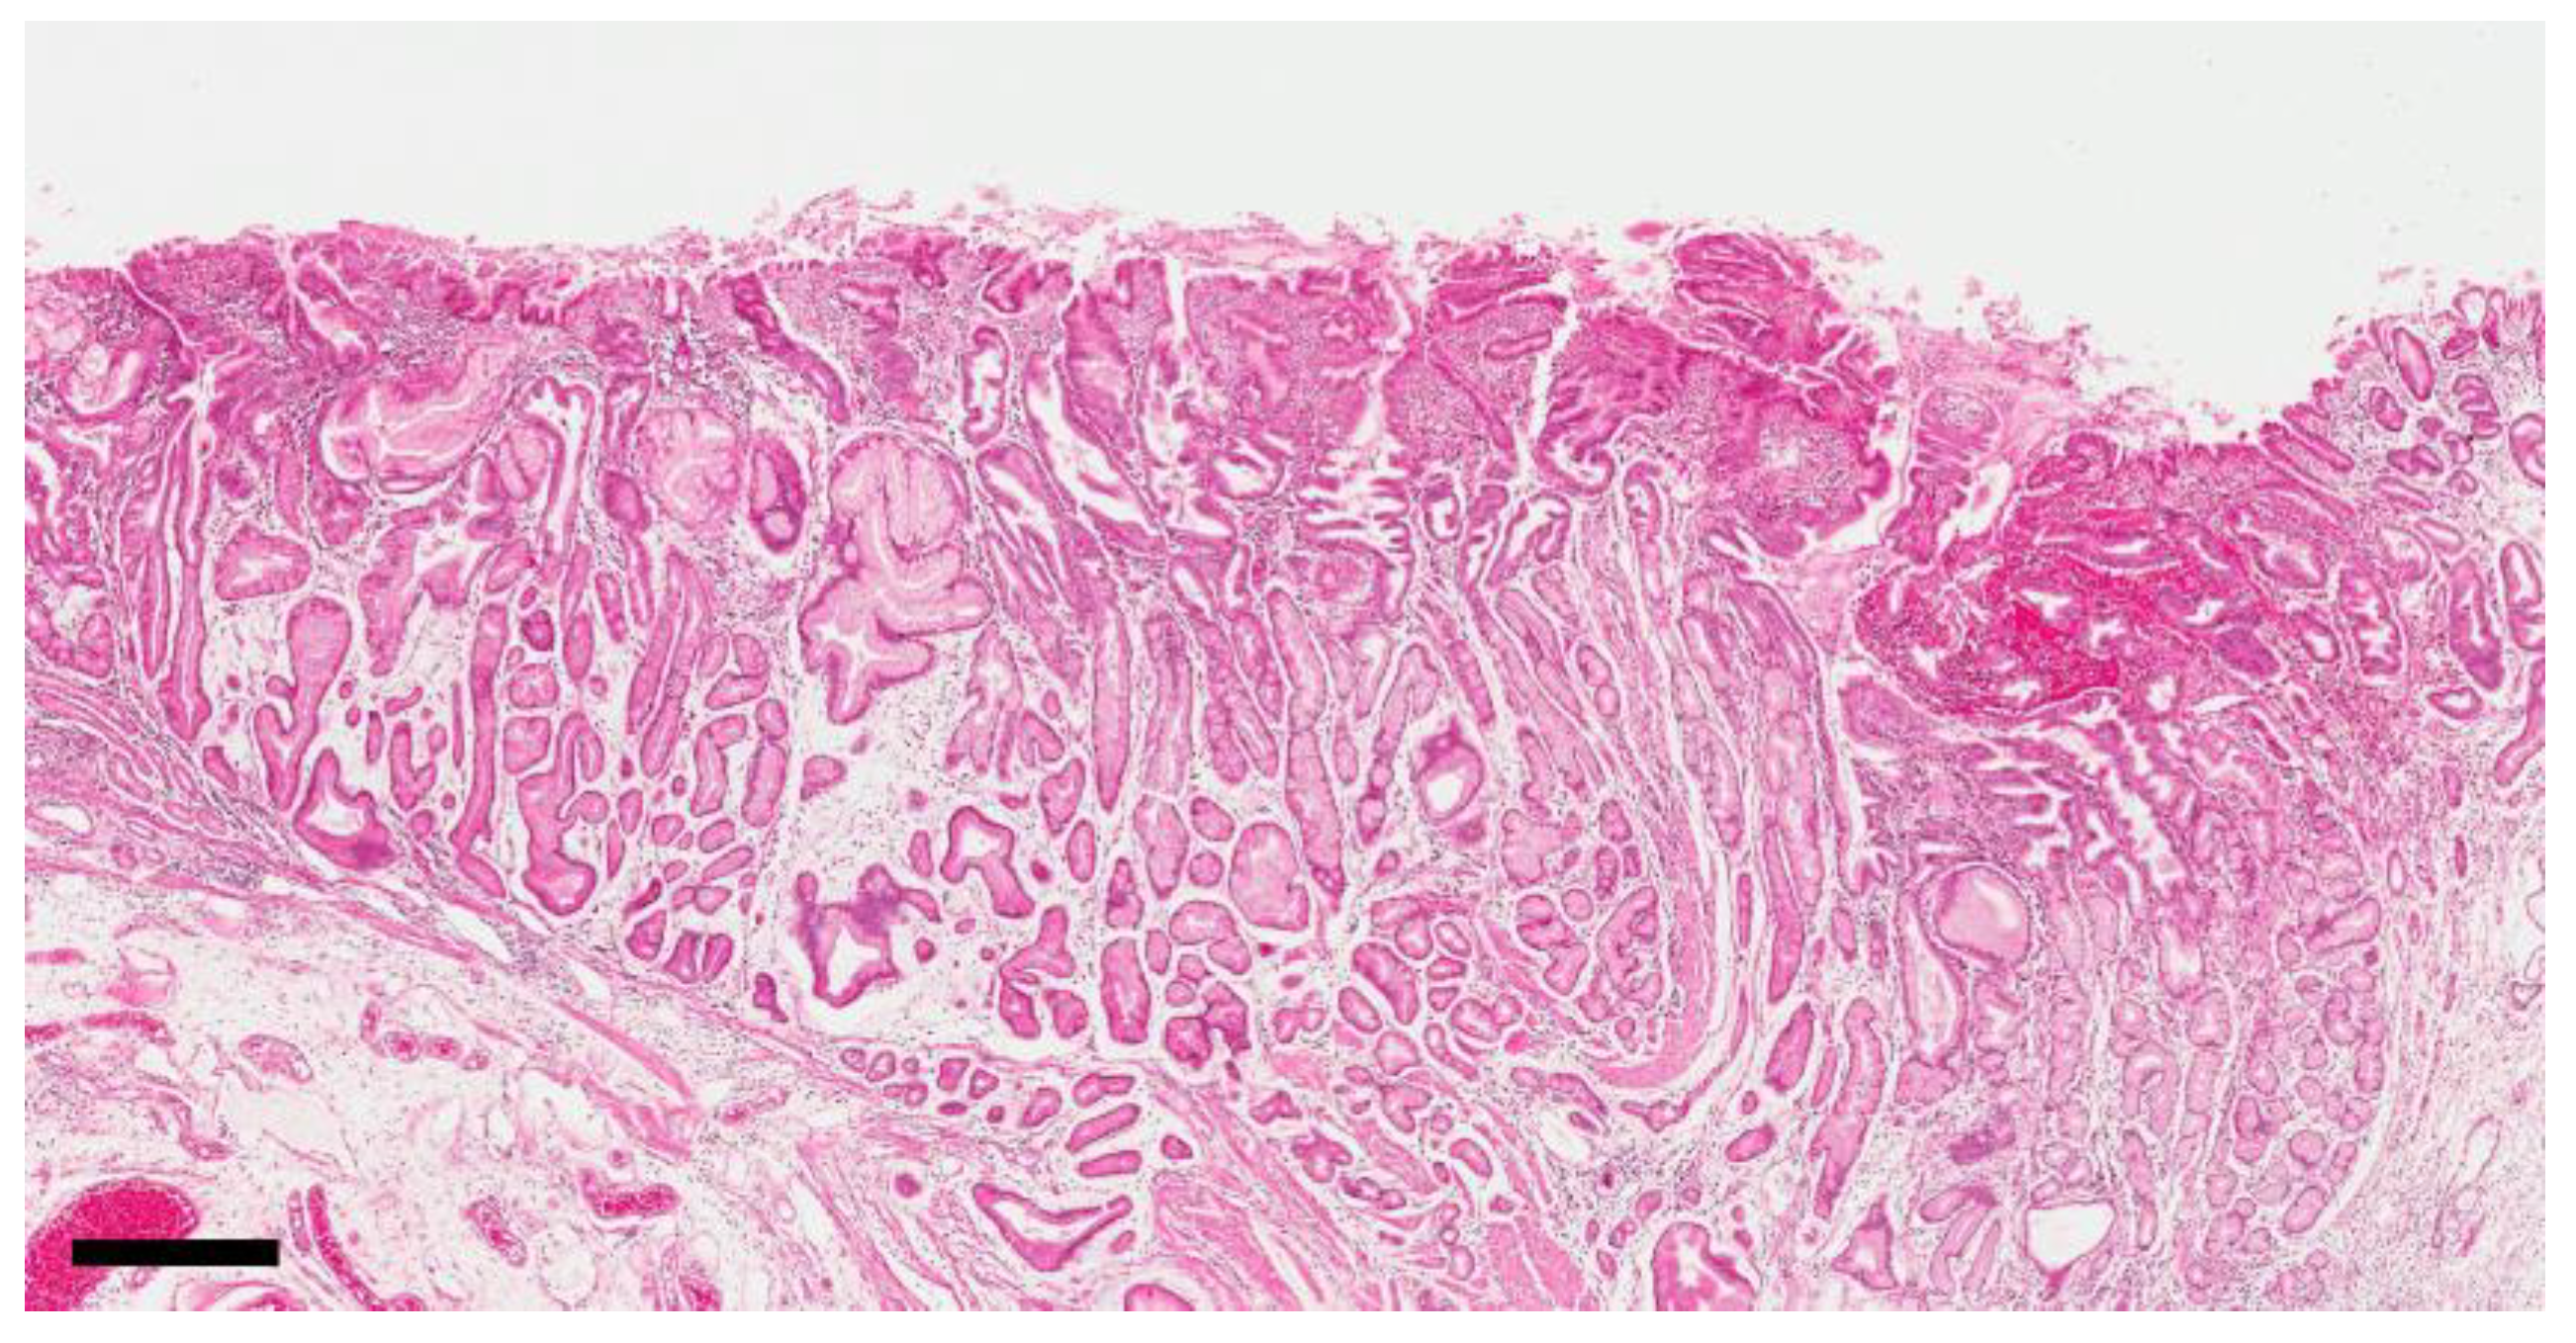

3.2. Distribution of Reflux-Induced Mucosal Changes in the Anastomosis Area

3.3. Differences in the Mucosa of the Anastomosis Area between Benign and Malignant Cases

3.4. Differences in the Background Mucosa around the Carcinoma between Benign and Malignant Cases